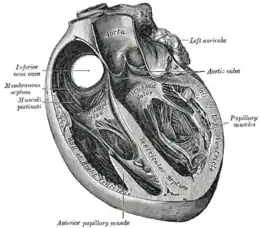

Section of the heart showing the ventricular septum. | |

The ventricular septum is directed obliquely backward to the right and curved with the convexity toward the right ventricle; its margins correspond with the anterior and posterior interventricular sulci. The lower part of the septum, which is the major part, is thick and muscular, and its much smaller upper part is thin and membraneous.[1]

The interventricular septum is the stout wall separating the ventricles, the lower chambers of the heart, from one another.

The ventricular septum is directed obliquely backward to the right and curved with the convexity toward the right ventricle; its margins correspond with the anterior and posterior longitudinal sulci. The greater portion of it is thick and muscular and constitutes the muscular interventricular septum. Its upper and posterior part, which separates the aortic vestibule from the lower part of the right atrium and upper part of the right ventricle, is thin and fibrous, and is termed the membranous ventricular septum.